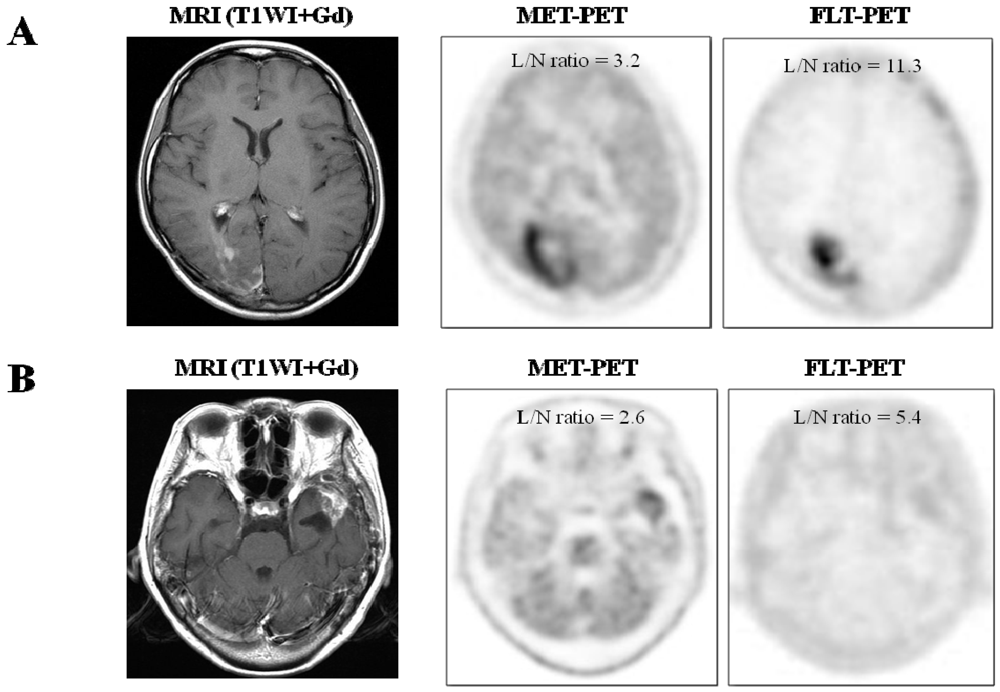

2.1.1. Visual Assessment

| 9 | 22 | F | Glioblastoma | 5.21 | 3.20 | 3.05 | 11.30 | Surgery | Recurrence |